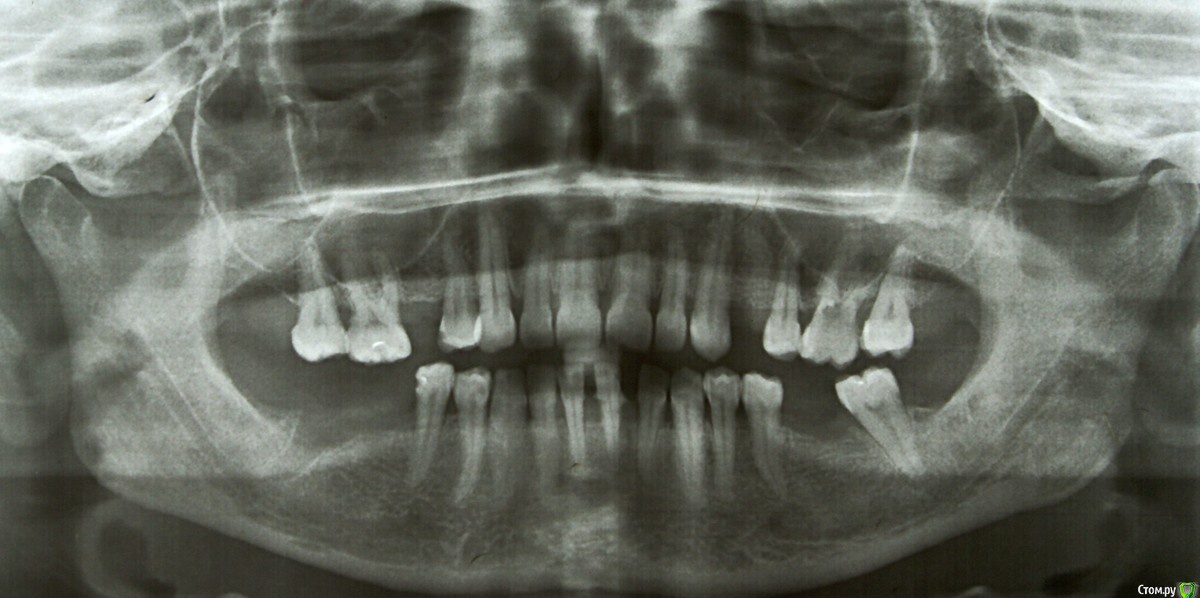

Shelly2000 Опубликовано 25 февраля, 2018 Поделиться Опубликовано 25 февраля, 2018 Здравствуйте! На консультациях у пародонтологов по приложенному панорамному снимку двое видят среднюю степень тяжести пародонтита, один - тяжелую.Подвижность зубов отсутствует. Подскажите, пожалуйста, какой диагноз правильный? Ссылка на комментарий

AndyAndy Опубликовано 25 февраля, 2018 Поделиться Опубликовано 25 февраля, 2018 По снимку все неплохо. Для определения тяжести процесса нужен очный осмотр с целью выявления глубины пародонтальных карманов, выделений из них, наличия зубных отложений, подвижности зубов (по снимку фронтальная группа снизу может быть подвижна) В целом, повторюсь, тяжелой формы я здесь не вижу, я даже генерализованной формы пародонтита не вижу 1 Ссылка на комментарий

AndyAndy Опубликовано 25 февраля, 2018 Поделиться Опубликовано 25 февраля, 2018 Спасибо за ответ! Осмотры неоднократно были. Пародонтальные карманы на всех зубах по-разному - от 0,5 до 5. Выделений никаких нет. Зубные отложения снимаются при чистке ультразвуком. Диагноз может зависеть от того, пойти на осмотр до такой чистки или после? Если это не генерализованная форма, то какая тогда? Может, это вообще не пародонтит?Выделяют локализованную и генерализованную. Повторюсь, исключительно по снимку, генерализованной тяжёлой формы не вижу. Есть участки где действительно могут быть вопросы, связанные с образованием карманов и потерей костной ткани. Наблюдаться у доктора пародонтолога необходимо регулярно по предписанию Ссылка на комментарий

Shelly2000 Опубликовано 26 февраля, 2018 Автор Поделиться Опубликовано 26 февраля, 2018 Есть участки где действительно могут быть вопросы, связанные с образованием карманов и потерей костной ткани. Спасибо Вам за подробный ответ!А ещё по снимку один из врачей увидел в верхней левом шестом зубе какую-то перфорацию. Можете прокомментировать? Ссылка на комментарий

AndyAndy Опубликовано 26 февраля, 2018 Поделиться Опубликовано 26 февраля, 2018 Все верно, этому зубу надо как минимум сделать прицельный снимок. Не буду разбрасываться диагнозами, так как нечетко видно что это Ссылка на комментарий